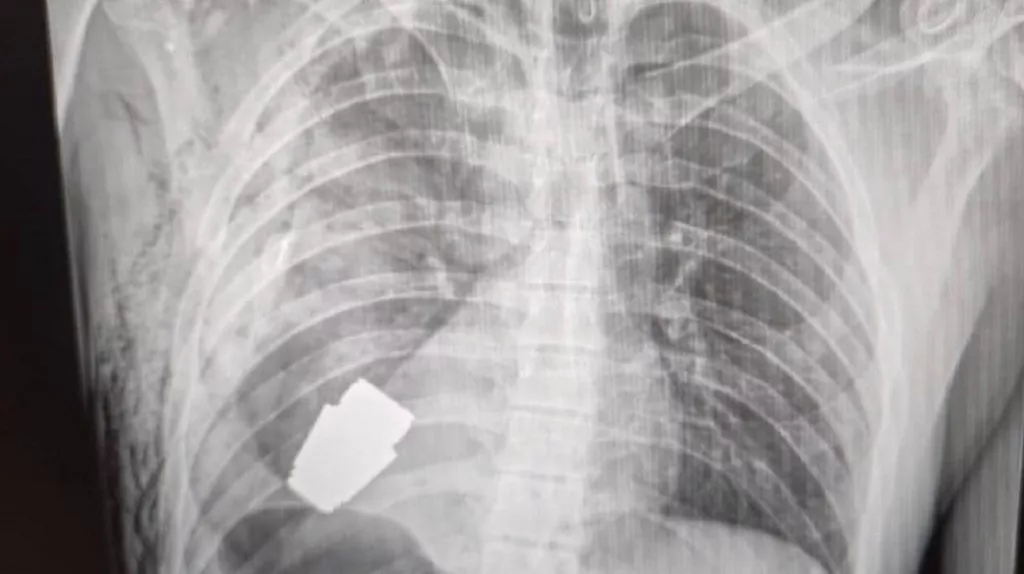

Кардіохірурги львівської дитячої лікарні св. Миколая прооперували п’ятимісячну дівчинку з Нововолинська, у якої діагностували вроджену ваду – дефект перегородки між шлуночками серця. Аби усунути її, лікарям довелося зупинити серце маляти. Оперували маленьку мініінвазивно, тобто через невеликий розріз, повідомляють на ...